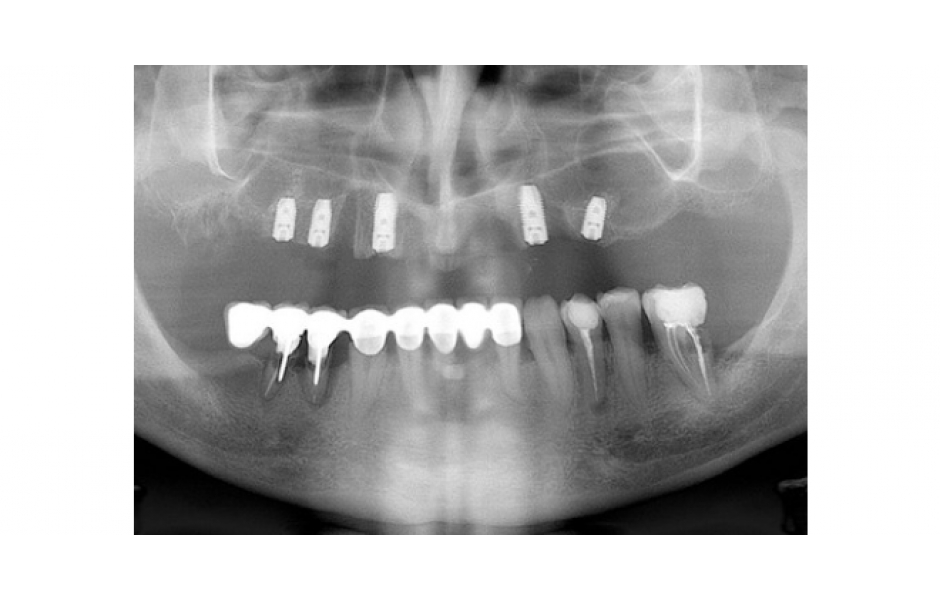

Stanko: „V tomto případě Nino vyjádřil přání zahájit ošetření pouze v horní čelisti. Prvním krokem v našem postupu bylo zhotovit panoramatický RTG snímek a CT sken. Na panoramatickém RTG snímku vidíme mnoho problémů se stávajícími zuby. Nino měl závažnou parodontózu, která postihovala všechny zuby v horní i dolní čelisti. Mnoho zubů zde selhávalo vlivem zubního kazu a dřívějších špatných dentálních náhrad. Jedinou schůdnou možností bylo extrahovat Ninovi všechny zuby v horní čelisti a rehabilitovat celý oblouk. Poté jsme promluvili s Ninem a vysvětlili mu problémy, které měl v horní čelisti a možnosti ošetření. Všichni jsme se shodli na tom, že by pro něj byla nejlepší možností náhrada kotvená šroubky. Poté jsme udělali CT sken Ninovy horní čelisti za účelem vyhodnocení našich chirurgických možností.“